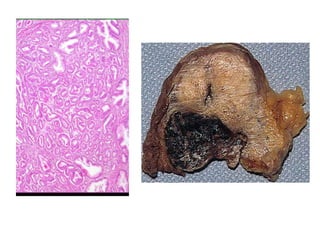

Figure- Coagulative necrosis

A. wedge-shaped kidney infarct (yellow).

B. Microscopic view of the edge of the infarct, with

normal kidney